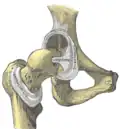

Та́зобе́дренный суста́в (лат. articulatio coxae) — чашеобразный, многоосный сустав, образованный полулунной поверхностью вертлужной впадины тазовой кости и суставной поверхностью головки бедренной кости. Вертлужная губа, сращённая с краем вертлужной впадины, углубляет последнюю.

Анатомия

Суставная капсула к тазовой кости прикрепляется по окружности вертлужной впадины, оставляя вертлужную губу внутри полости сустава. К бедренной кости капсула прикрепляется спереди вдоль межвертельной линии, сзади — немного отступая кнутри от межвертельного гребня. Таким образом, шейка бедра располагается в суставной полости.

Связка головки бедра (лат. ligaméntum cápitis fémoris), находящаяся внутри суставной капсулы, препятствует чрезмерному приведению и наружной ротации бедра. Кроме этой связки тазобедренный сустав укреплён несколькими толстыми, прочными связками, расположенными как в толще капсулы, так и на её поверхности, а именно: